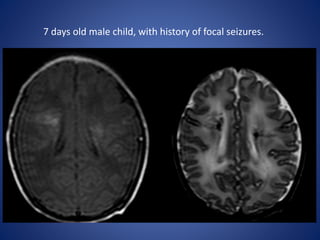

7 days old male child, with history of focal seizures.

DWI ADC

7 days oldmale child, with history of focal seizures.

• 45.